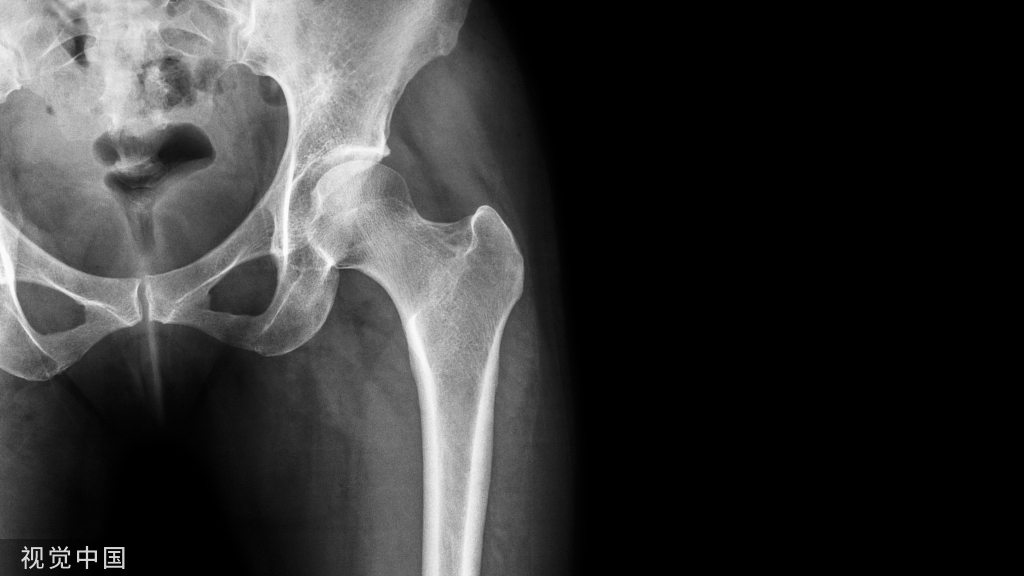

寰椎骨折又名Jefferson骨折(因由Jefferson于1920年首次报道,故此命名)。环形的寰椎遭受轴向压缩和头部向后、下转伸时,暴力经枕骨髁作用于寰椎侧块,并引起寰椎骨环爆裂(散)骨折。寰椎的前弓与后弓双侧骨折,以致侧块被挤压而向四周分离

主要介绍颈椎开口位的X线平片表现:开口位可发现寰椎左右增宽,且与齿突的距离双侧常呈不对称状。如双侧侧方移位总和超过7mm者,则表示寰椎横韧带断裂、寰椎骨折。

正位与齿状突对比似双侧开门样增宽,为此加深记忆,故得此名,如有不妥,敬请谅解(小编)。